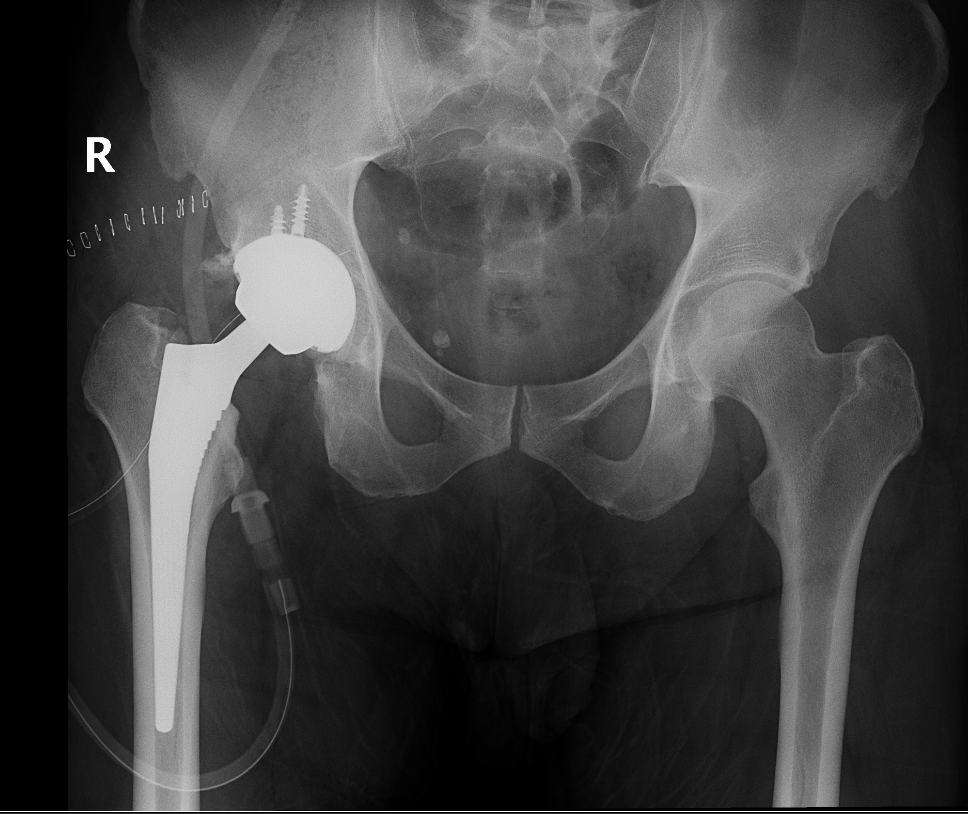

The surgery is performed under general anesthesia. During the procedure a surgical cut is made over the hip to expose the hip joint and the femur is dislocated from the acetabulum. The surface of the socket is cleaned and the damaged or arthritic bone is removed using a reamer. The acetabular component is inserted into the socket using screws or occasionally bone cement. A liner made of plastic, ceramic or metal is placed inside the acetabular component. The femur or thigh bone is then prepared by removing the arthritic bone using special instruments, to exactly fit the new metal femoral component. The femoral component is then inserted to the femur either by a press fit or using bone cement. Then the femoral head component made of metal or ceramic is placed on the femoral stem. All the new parts are secured in place using special cement. The muscles and tendons around the new joint are repaired and the incision is closed.